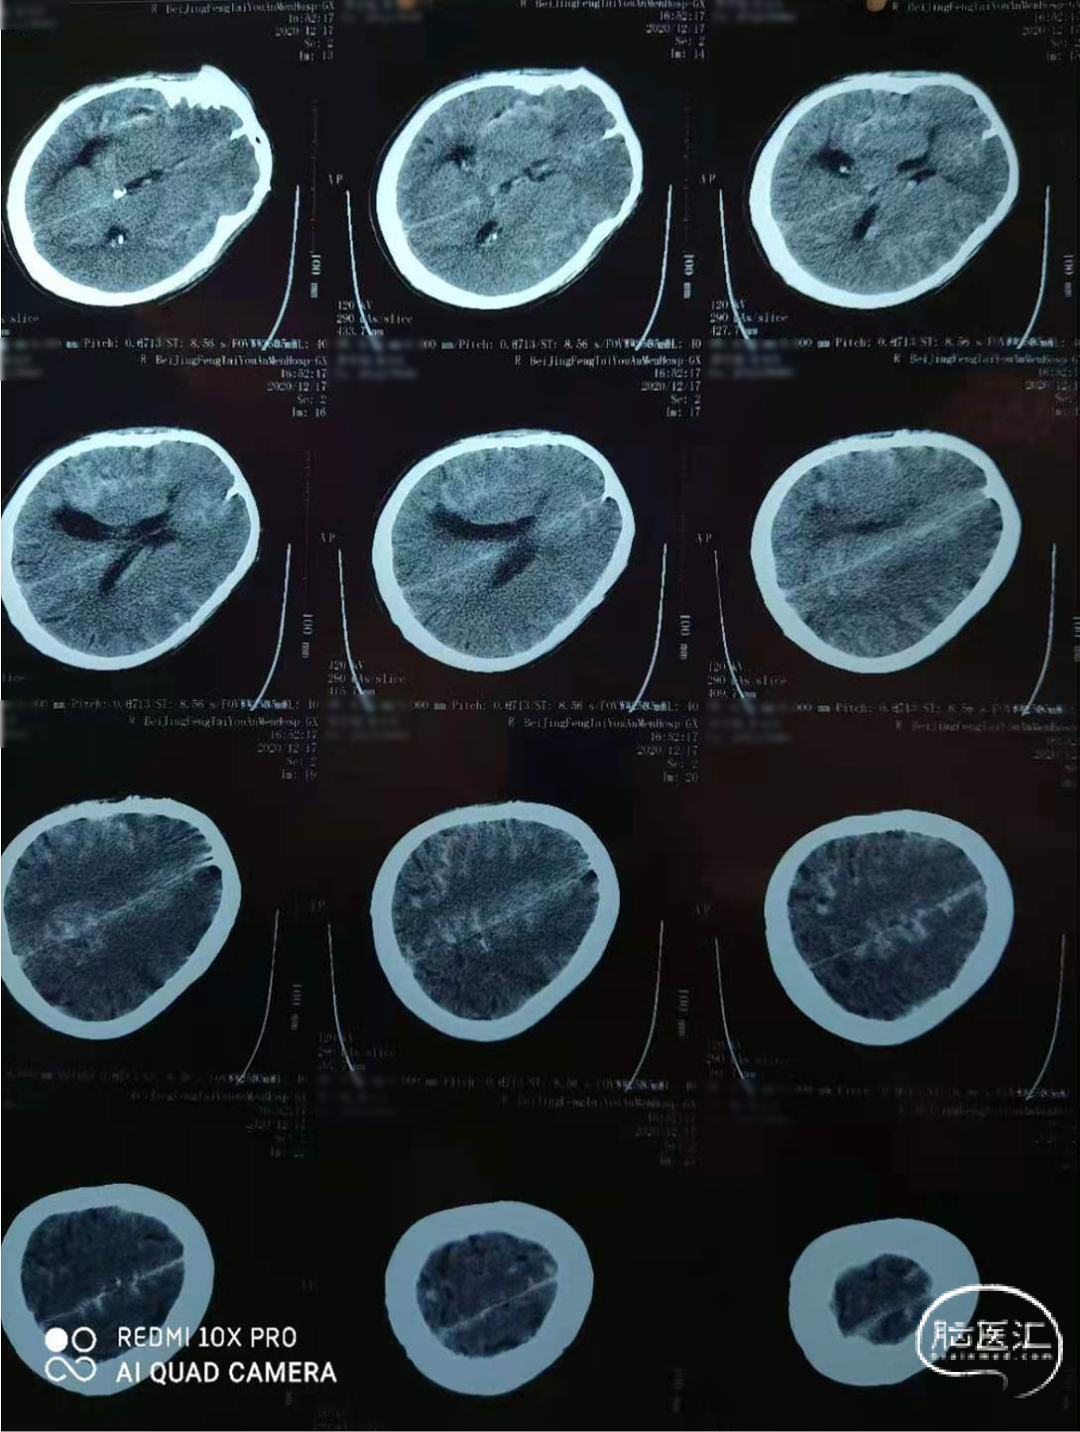

术前影像

术前头颅CT

现病史:患者6小时前在家中无明显诱因突发头疼伴恶心、呕吐,无意识不清,前往固安县医院行头颅CT示广泛蛛网膜下腔出血,考虑颅内动脉破裂出血。为行手术治疗,前来我院,急诊以“蛛网膜下腔出血”收入科。